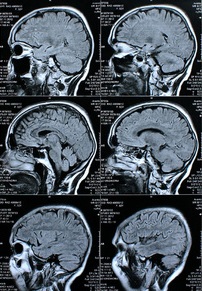

Gehirne im Querschnitt: Informationsfluss kompliziert Bild: pixelio.de, Rike